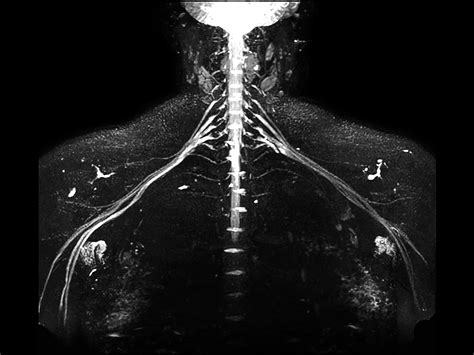

When chronic pain, numbness, or weakness persists without a clear explanation from standard diagnostic imaging, physicians may turn to more specialized techniques to pinpoint the source of the problem. One such advanced diagnostic tool is MRI Neurography. Unlike conventional MRI scans, which are primarily designed to visualize bones, muscles, and soft tissues, this specialized imaging technique is specifically engineered to provide detailed, high-resolution views of the peripheral nerves throughout the body. By enhancing the visualization of nerve fibers, MRI Neurography allows clinicians to detect subtle abnormalities, compressions, or lesions that might otherwise go unnoticed, playing a critical role in the accurate diagnosis and management of complex neurological conditions.

At its core, MRI Neurography is a sophisticated imaging protocol that utilizes powerful magnetic fields and radiofrequency pulses to create detailed maps of the peripheral nervous system. While traditional MRI sequences are effective for identifying large structural issues, they often lack the contrast necessary to differentiate nerve tissue from surrounding structures like fat, connective tissue, or blood vessels.

To overcome this, this specialized imaging employs specific pulse sequences designed to suppress the signal from fat—which often obscures nerve detail—while enhancing the signal from water-rich tissues like nerves. This process effectively makes the nerves "light up" on the resulting images, allowing radiologists to assess their anatomy, signal intensity, and trajectory in high detail.